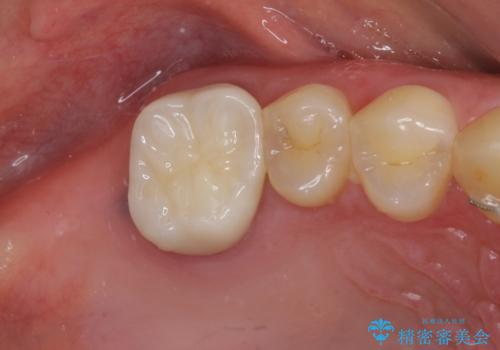

- 前歯の隙間と奥歯の目立つ銀歯を気にして来院された患者様です。

インビザラインにより下顎前歯の隙間を閉じるとともに、奥歯の咬み合わせを改善させることとしました。

矯正治療後には、銀歯のクラウンをセラミッククラウンへ替える補綴治療を行うこととしました。